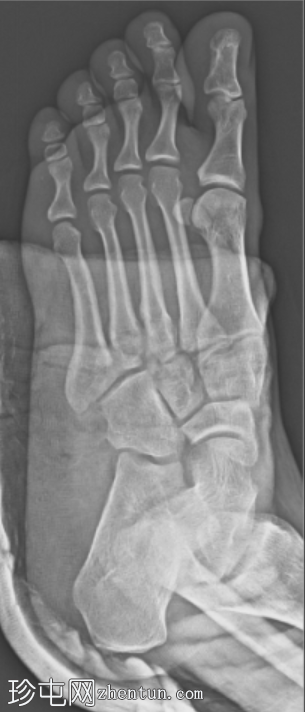

正位片

可见正常的M2-C2对位被破坏,第二跖骨基底部向外侧移位。C1-M2间隙以及第一和第二跖骨基底部之间的跖骨间隙增宽,符合Lisfranc韧带断裂的表现。在中间楔骨附近可见一小块相邻骨碎片,呈斑点征。